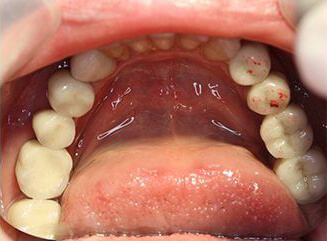

Проблема. Множественные кариозные поражения зубов, высокая степень подвижности зубов

Решение. Из-за плохого стоматологического прогноза оставшиеся зубы были удалены, а в верхнюю и нижнюю челюсти были установлены четыре зубных имплантата. На имплантаты установлены металлокерамические коронки.